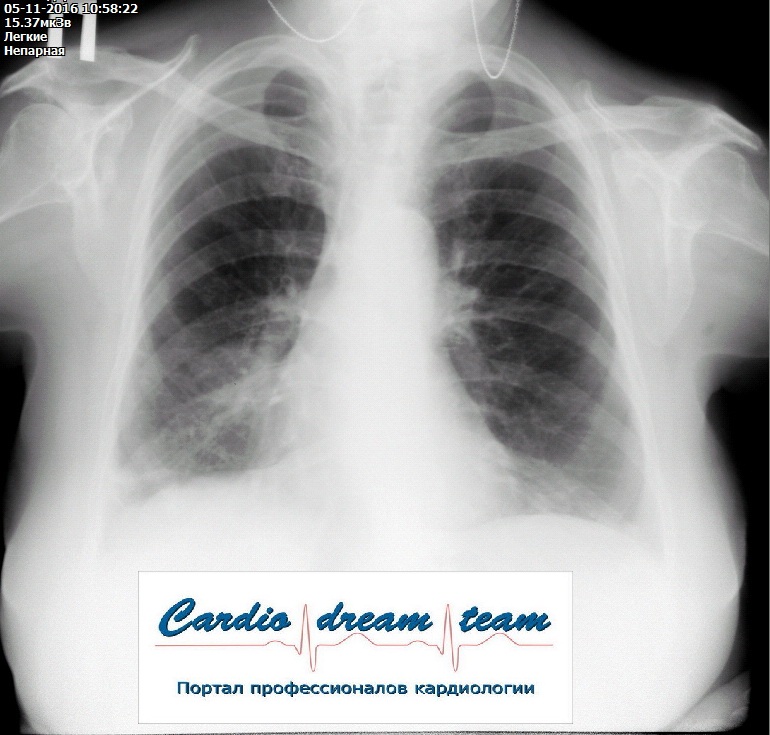

На рентгене гиповентиляция - признак центрального рака

Обсуждалось в Госпитале Ослабленных Сердец